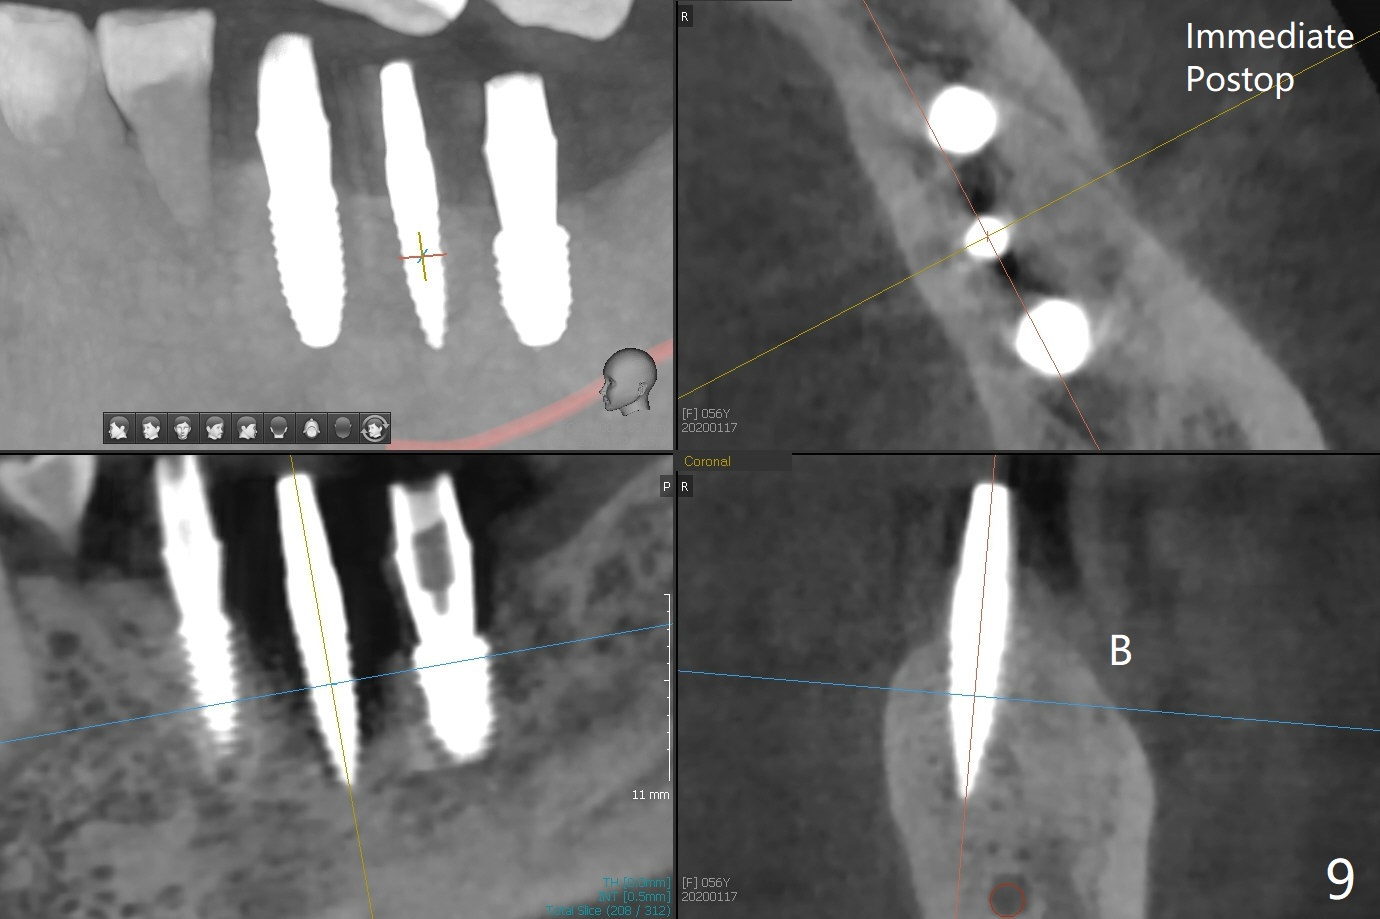

PA is taken after a 2.2 mm drill reaches the depth at #12, since osteotomy is initiated in the mesial slope of the socket (Fig.1 red dashed line) and the neighboring root (*) slightly curves distal. A 8.6x5 mm healing abutment is used to close the socket with the large mesiodistal space after bone graft (Fig.2 *). In contrast, the socket at #20 is large; a 4.5x4.5(3) mm cementation abutment is placed for an immediate provisional to keep autogenous bone (harvested from the site of #18) in place (Fig.3). Six months postop, the patient does not want implant FPD. She wants an additional implant at #19. Since the space between the implants #18 and 20 is 9.41 mm, a narrow implant is indicated (3 or 3.5 mm, Fig.4), in spite of the sufficient buccolingual width (Fig.5). The position and trajectory of the 1.2 mm initial drill and 3x10(2) mm 1-piece implant are acceptable with free hand (Fig.6,7). After 3-4 more turns, panoramic X-ray (Fig.8) and CT (Fig.9) are taken for 28-30 guide. It appears that the 1-piece implant is placed acceptable buccolingual (Fig.9 B). The implants at #12,18,20 (4.5 months postop with guide) are shown in Fig.10-12. It appears that guided surgery is superior in buccolingual position and trajectory to free hand. There is crestal remodeling without implant thread exposure 11 months postop (Fig.13).